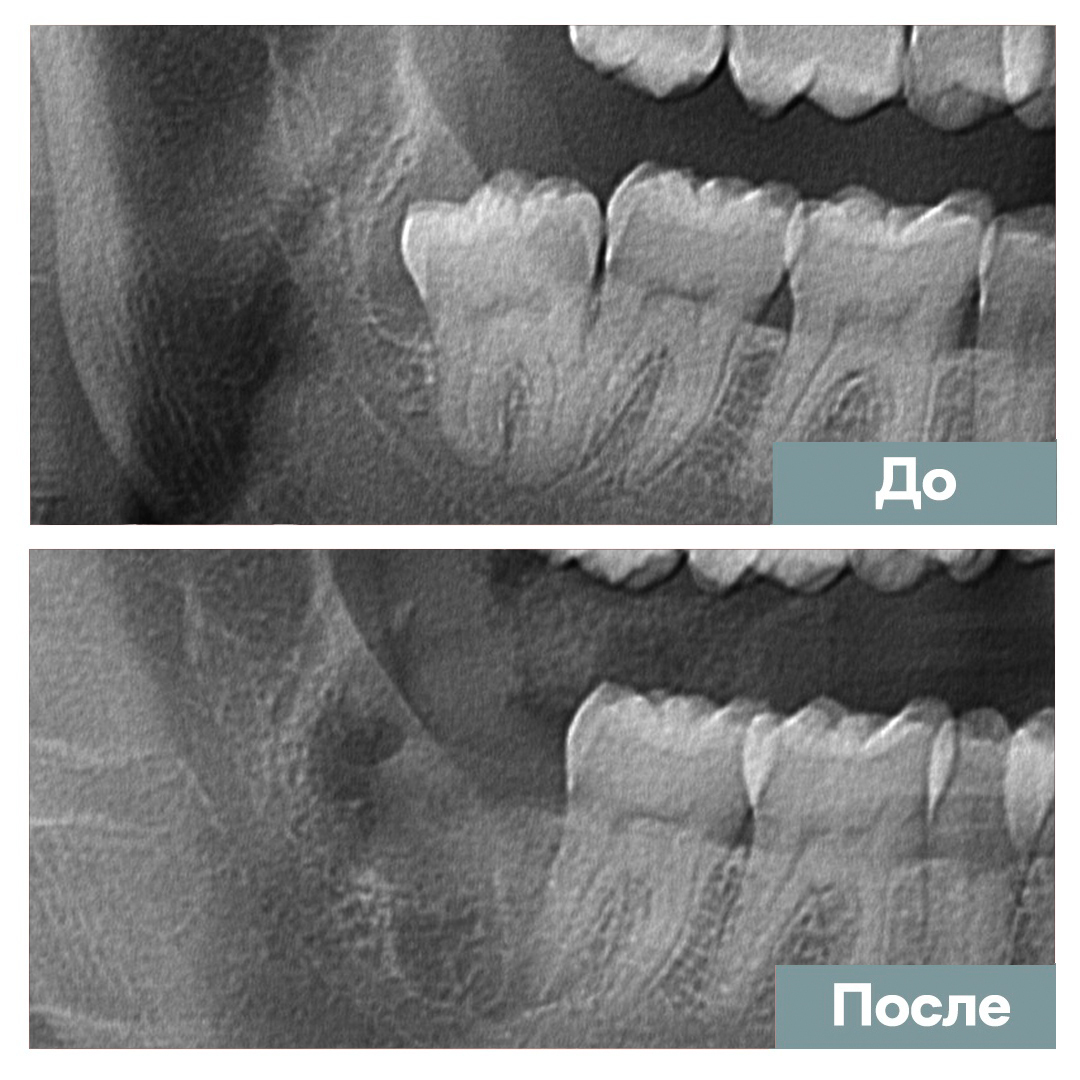

Удаление сложного "зуба мудрости"

Мазанов